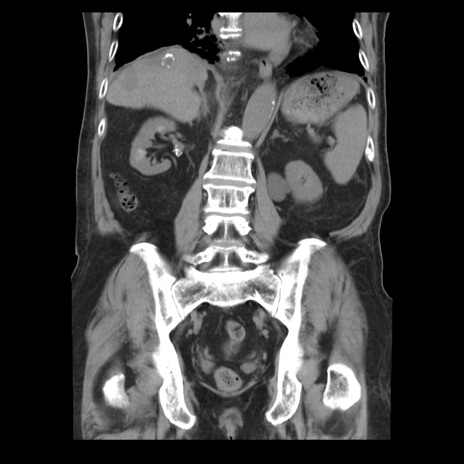

横断像

【症例】70歳代男性

【主訴】腹痛

【現病歴】肝硬変・肝細胞癌にてかかりつけの方。約9時間前に食後より腹痛出現。症状が徐々に増悪し、嘔吐出現したため来院。

【既往歴】肝硬変、肝細胞癌(RFA、TACE後)

【身体所見】意識清明、表情苦悶様、BT 36℃、BP 129/78mmHg、P 88bpm、SpO2 97%(RA)、右上腹部から心窩部にかけて圧痛あり、反跳痛なし、筋性防御あり。

【データ】WBC 5800、CRP 0.16